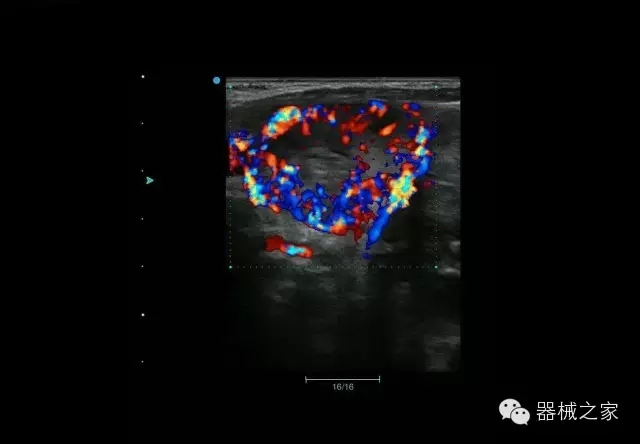

臨床圖片賞析

睪丸低速血流

臍帶血流

頸動(dòng)脈頻譜